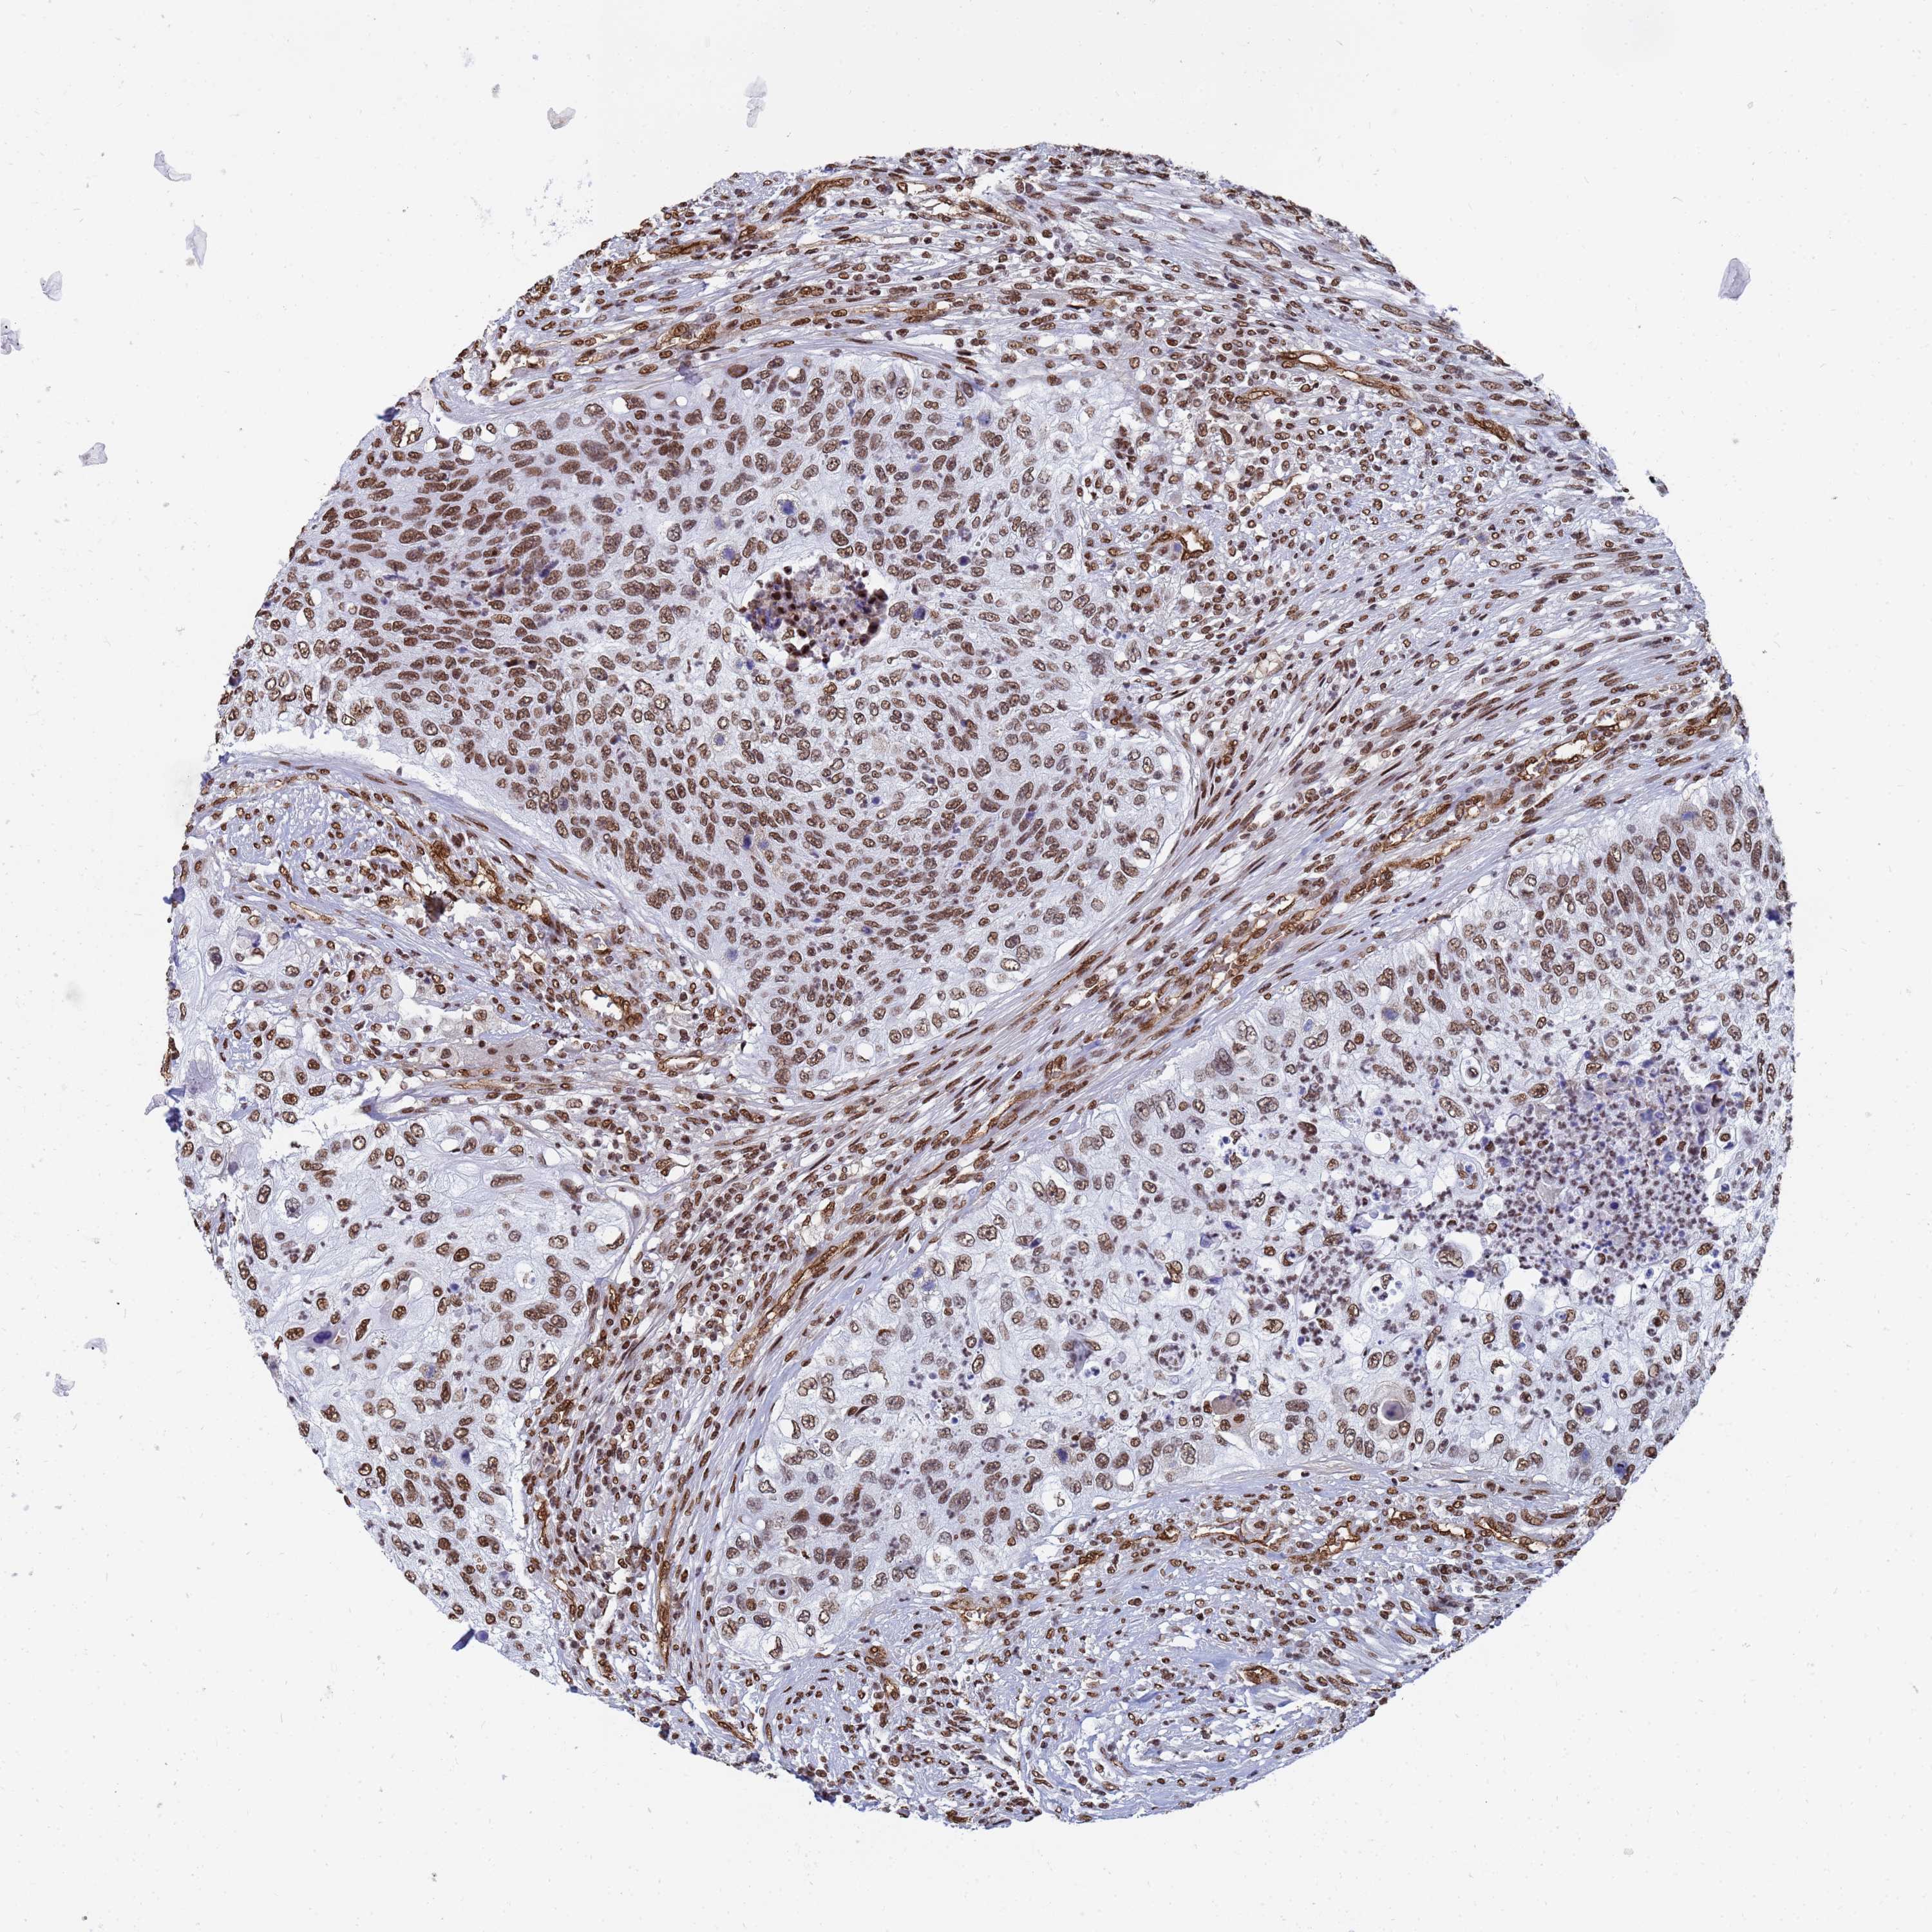

UROTHELIAL CANCER - Protein expressioni

A mouse-over function shows sample information and annotation data. Click on an image to view it in a full screen mode. Samples can be filtered based on level of antibody staining by selecting one or several of the following categories: high, medium, low and not detected. The assay and annotation is described here.

Note that samples used for immunohistochemistry by the Human Protein Atlas do not correspond to samples in the TCGA dataset.

Antibody stainingi

Antibody staining in the annotated cell types in the current human tissue is reported as not detected, low, medium, or high, based on conventional immunohistochemistry profiling in selected tissues. This score is based on the combination of the staining intensity and fraction of stained cells.

Each image is clickable and will lead to virtual microscopy that enables deeper exploration of all samples and also displays staining intensity scores, fraction scores and subcellular localization as well as patient and tissue information for each sample.

Antibody HPA045785

Staining

High

Medium

Low

Not detected

Intensity

Strong

Moderate

Weak

Negative

Quantity

>75%

75%-25%

<25%

None

Location

Nuclear

Cytoplasmic/membranous

Cytoplasmic/membranous,nuclear

Urothelial carcinoma, High grade

Urothelial carcinoma, Low grade